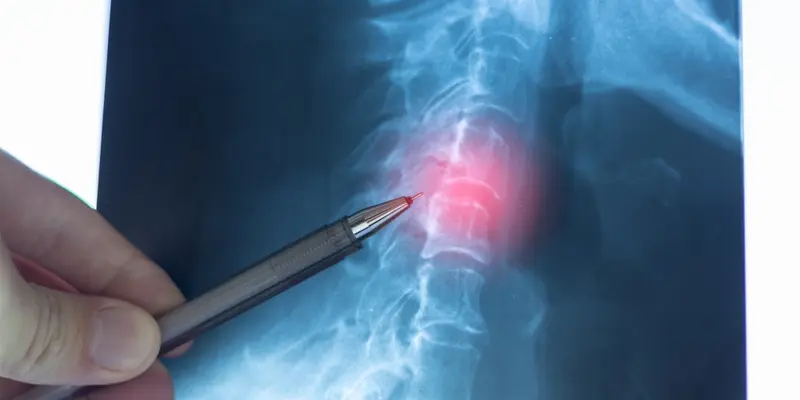

Chụp X-quang: Phương pháp này cung cấp hình ảnh cơ bản về cấu trúc xương cột sống, giúp phát hiện những bất thường và các khối u tiềm ẩn. Dù đơn giản, X-quang vẫn là bước khởi đầu hữu ích để nhận diện các thay đổi trong tủy sống.